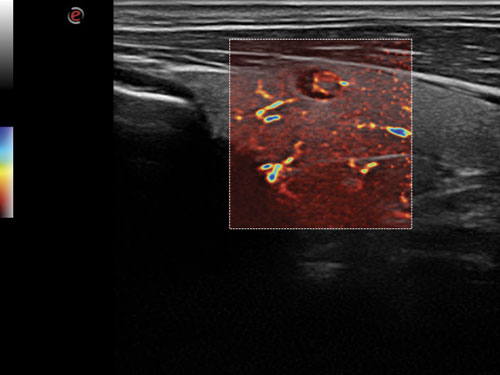

microV: Hemodynamické hodnocení s vysokou citlivostí a vysokým prostorovým rozlišením pro charakterizaci vaskularizace lézí ve všech klinických aplikacích, rychlé a neinvazivní.